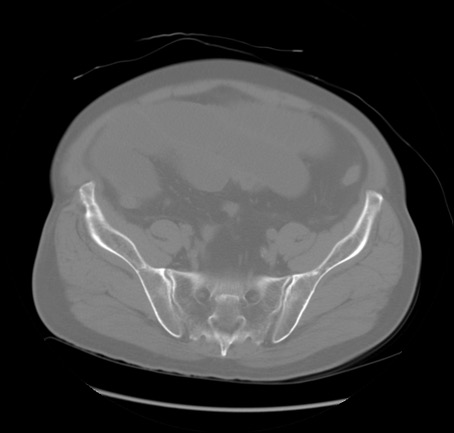

症例20(横断像)

【症例】 60歳代男性

【主訴】 腹部膨満、嘔吐

【現病歴】5日前頃より倦怠感を認め食事量減少し4日前の朝嘔吐、食事摂取困難となった。 3日前近医受診し点滴施行され整腸剤などを処方された。 当日他院を受診し、腹部膨満著明、炎症反応の上昇(CRP10.8、WBC11200)あり、紹介受診となる。

【身体所見】 意識JCS1 受け答えがはっきりしないBP 111/57mHg、 P 67bpm、、BT35.2°C、SpO2 97%(RA)、 腹部:膨隆、打診で鼓音あり、全体的に圧痛有り、腸蠕動音(-)、反跳痛ははっきりせず。

【データ】WBC 11400、CRP 14.20